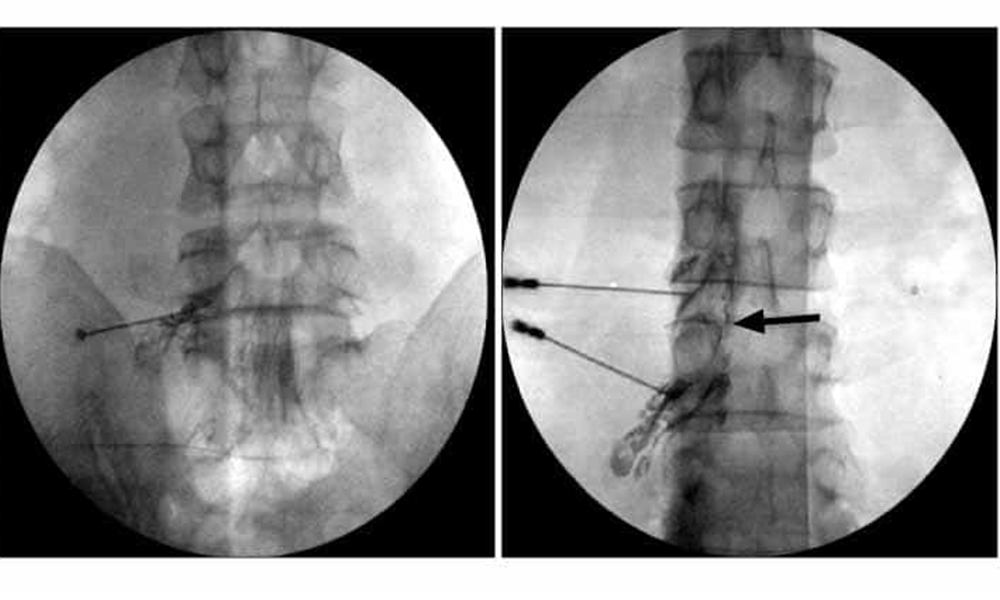

- PERCUTANEOUS TRANSFORAMINAL EPIDURAL STEROID INJECTION

- PERCUTANEOUS ENDOSCOPIC LUMBAR DISKECTOMY

1. Percutaneous trasforminal imjection Therapy

2. Per-Cutaneous Endoscopic diskectomy